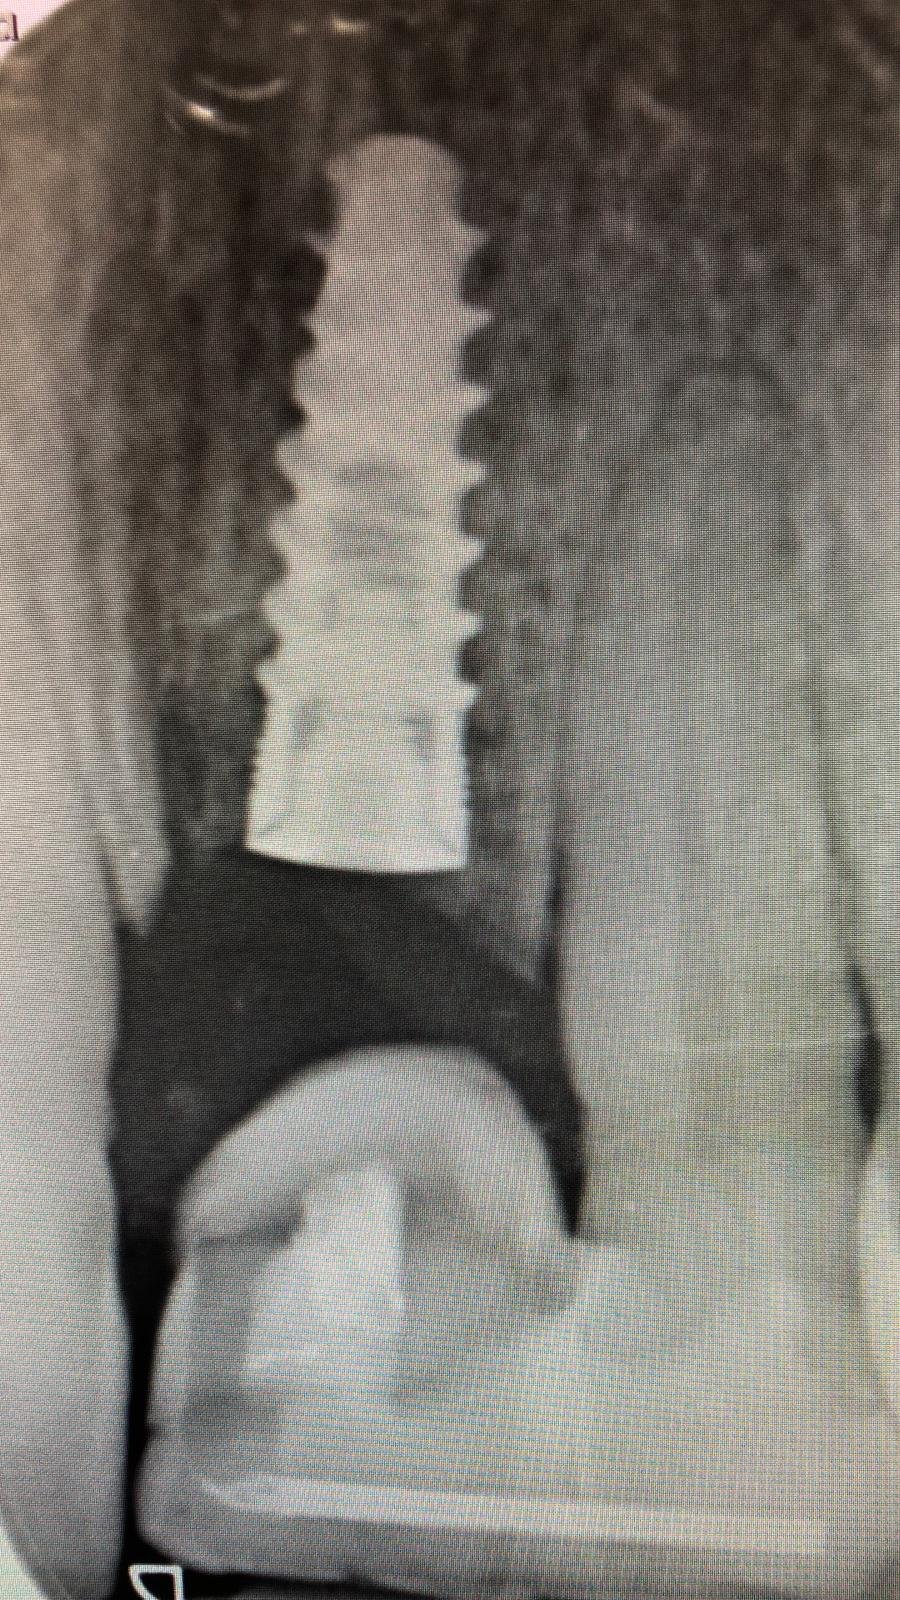

Paciente acude por molestias en segundo cuadrante. En la exploración detectamos prótesis sobre implantes en 22 y 23 con movilidad. En la rx periapical observamos que es una prótesis cementada [...]